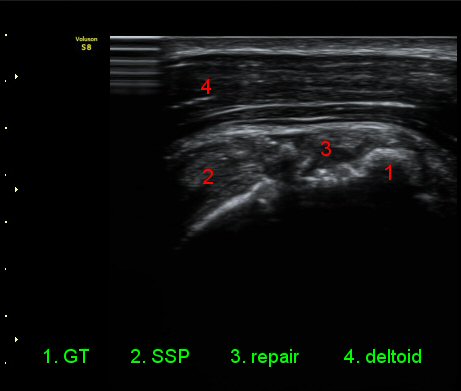

¾î±ú¸¦ ³»Àü, ³»È¸Àü, ½ÅÀüÇÏ¿© ±Ø»ó°Ç°Ë»ç¿¡¼­ ±Ø»ó°Ç ÆÄ¿­ ÈÄ ¼ö¼úÇÑ ¼Ò°ß, ±Ø»ó°ÇÀÇ

Àú¿¡ÄÚ ºÎÁ¾°ú ºÎºÐÀû ÆÄ¿­, °í¿¡ÄÚ ºÀÇÕ»ç, ´ë°áÀýÀÇ ºÒ±ÔÄ¢º¯È­,À» º¸¿©ÁØ´Ù(»çÁø 6, 7, 8, 9)